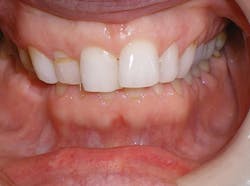

Case 2: 48-year-old female: 15-month clear aligner treatment. This case demonstrates an improvement in a remodeled alveolar complex and an increase in vertical dimension. Case and photos courtesy of Dr. Ben Miraglia.

Before: V-shaped arch. After: U-shaped arch.

Before: Severe deep bite. After: Improved vertical dimension.